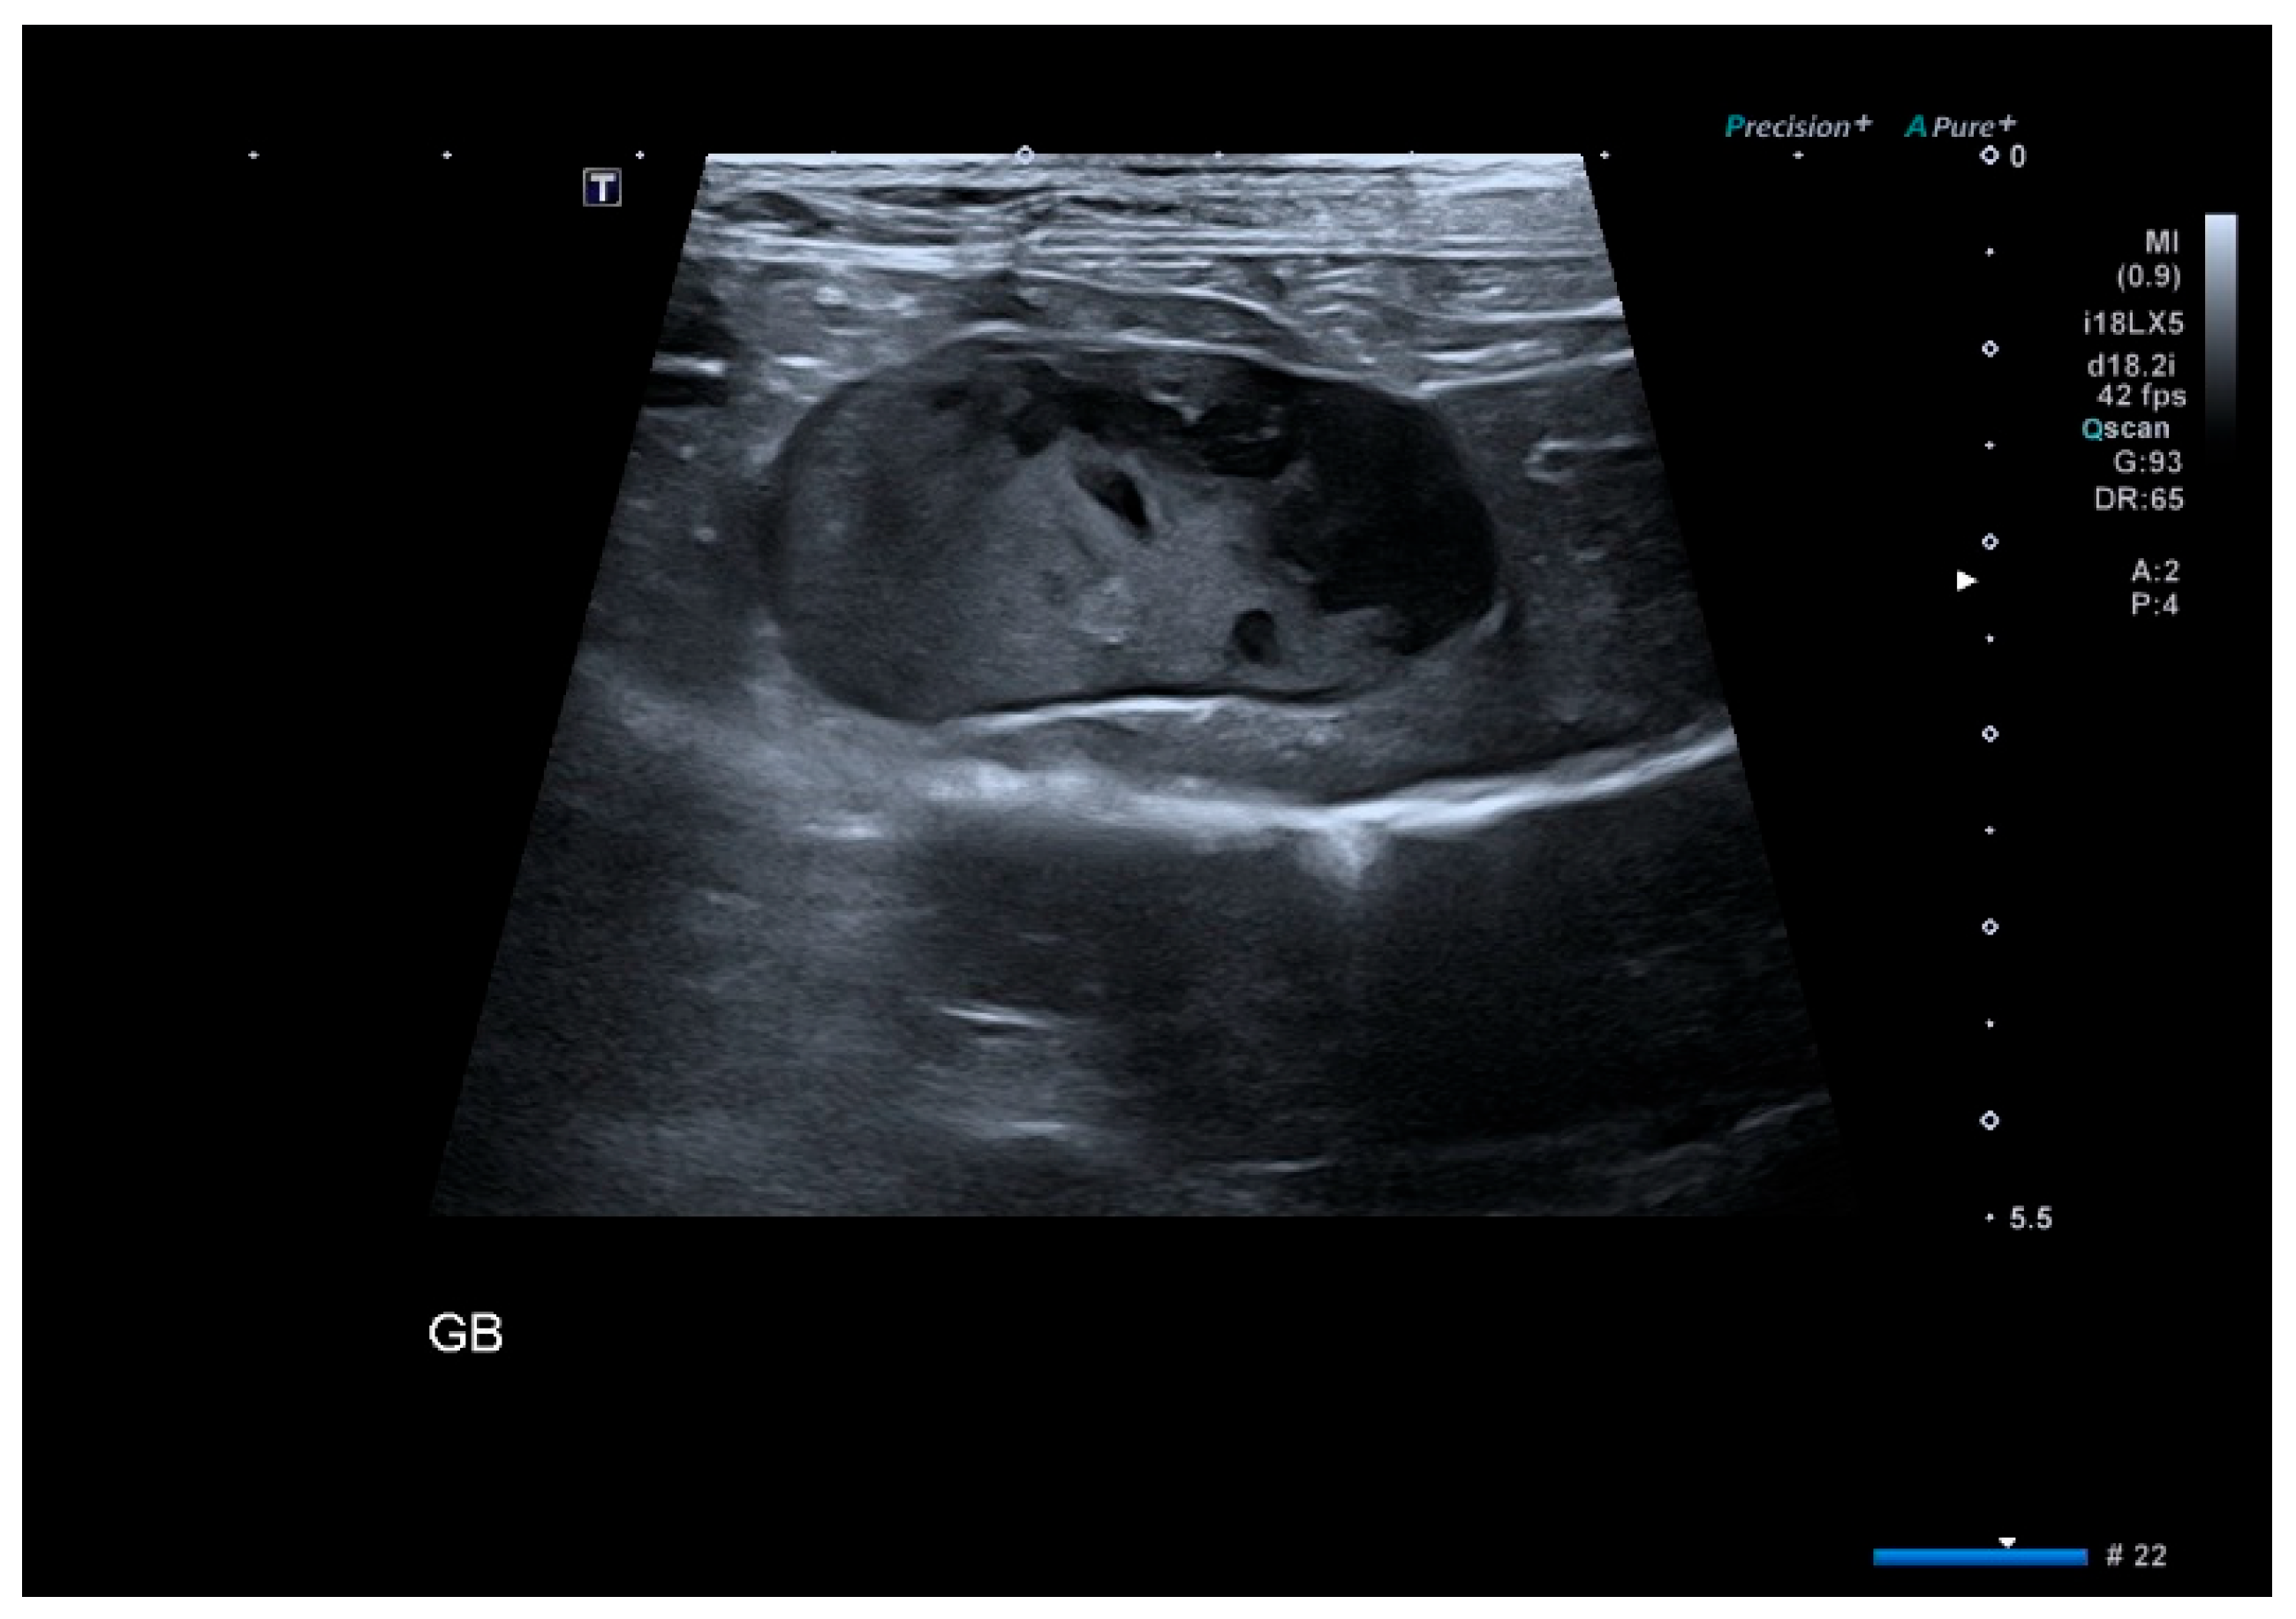

2.3. Imaging Evaluation

3.3. Ultrasound Findings